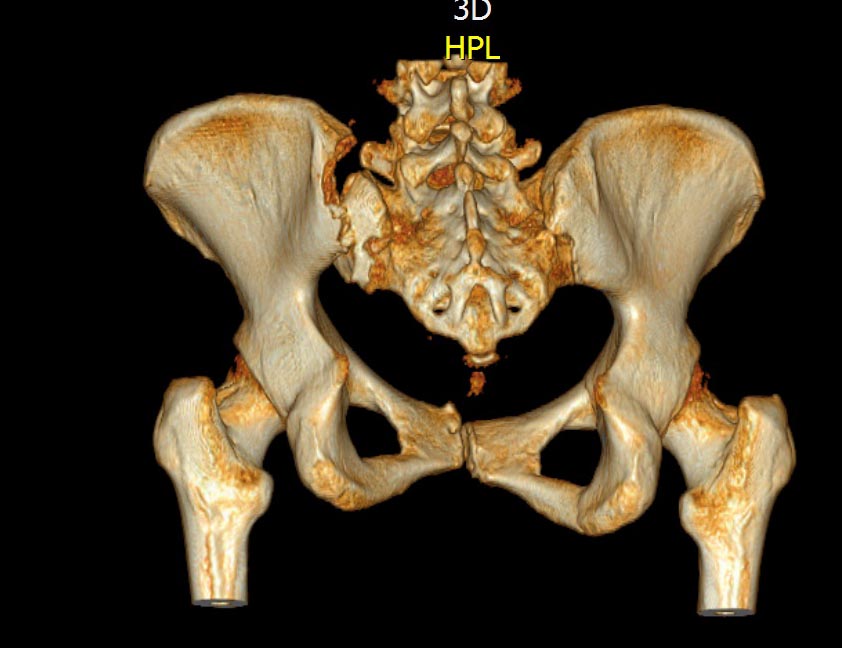

КТ, при детальном рассмотрении виден перелом задних отделов крыла подвздошной кости

KT